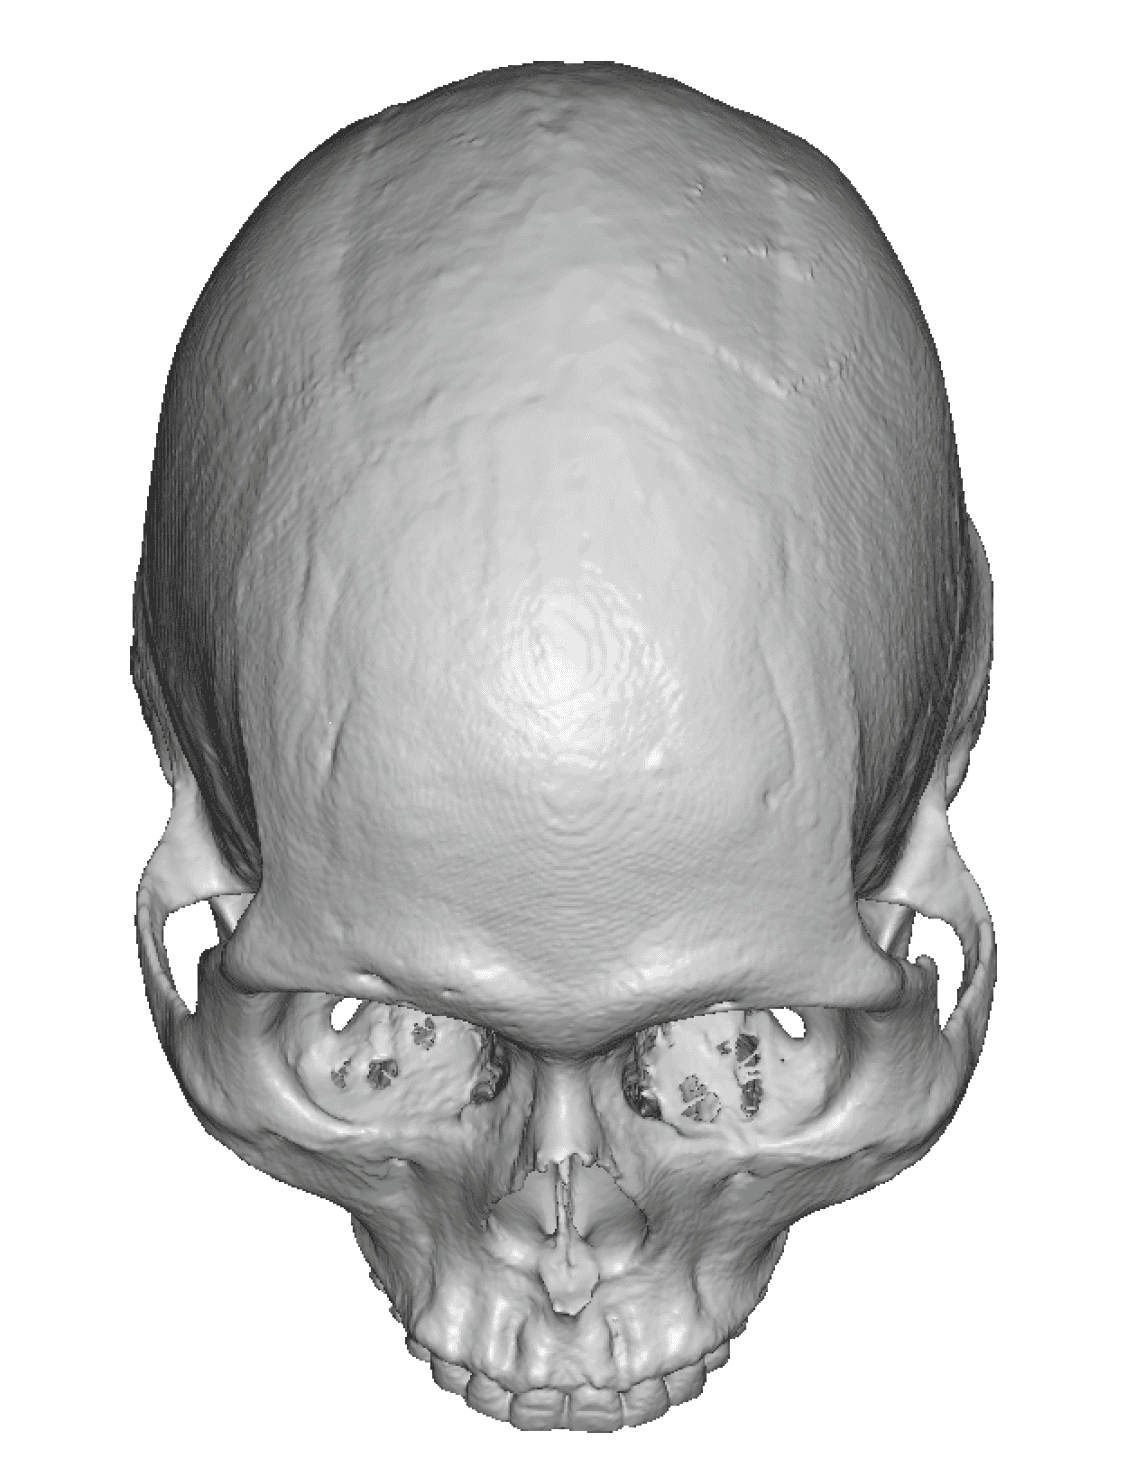

Severe narrowing skull deformity from prior sagittal craniosynostosis repair as an adult.

Complete replacement of entire skull by a custom implant with temporal fat injections.

Severe narrowing skull deformity from prior sagittal craniosynostosis repair as an adult.

Complete replacement of entire skull by a custom implant with temporal fat injections.